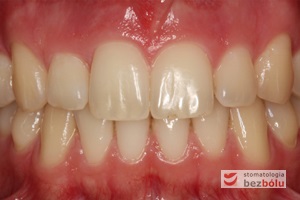

Młody 28-letni, pogodny, stale uśmiechnięty pacjent zgłosił się celem korekcji wad zębowych ograniczających pełną ekspresję uśmiechu. Głównym problemem był dodatkowy siekacz boczny (dwójka) po stronie prawej w łuku górnym. Dodatkowy ząb spowodował stłoczenia pozostałych zębów w łuku górnym oraz przesunięcie linii pośrodkowej. Obliczenia dostępnego miejsca dla siekacza bocznego wpłynęły na wybór zęba przeznaczonego do ekstrakcji. Usunięto dwójkę ustawioną dowargowo, zaś jej „siostrę bliźniaczkę” skierowaną w stronę podniebienia wprowadzono do łuku zębowego w drodze leczenia ortodontycznego. Problemem było szczelne zamknięcie szpary poekstrakcyjnej z powodu nadmiaru miejsca w kości. Wyrównano linię pośrodkową. Leczenie przeprowadzono jednym łukiem ortodontycznym górnym, dolny łuk zębowy nie wymagał założenia aparatu. Po zdjęciu zamków korekcję detali przeprowadzono z użyciem pozycjonera wykonanego w technice termoformingu. Stabilizację efektów leczenia zapewnił stały retainer klejony do powierzchni podniebiennych siekaczy górnych.

Leczenie ortodontyczne: planowanie i aktywna faza leczenia, leczenie retencyjne – lekarz stomatolog Magdalena Żywicka i lekarz stomatolog Marta Pakuła